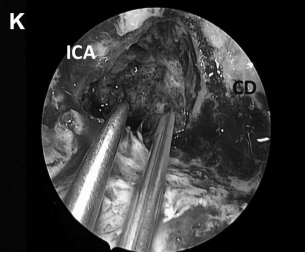

▼磨除骨质,暴露右侧斜坡旁的颈内动脉(ICA),注意血管保护(A)

▼进行斜坡凹陷处(CD)和海绵窦内壁骨质磨除,暴露肿瘤包膜的内侧边缘(B)

▼(K)使用TachoSil、纤维蛋白胶封闭颅腔

▼(L)使用鼻中隔瓣(NSF)完成封闭。CC,囊包膜;PFD,后颅窝硬脑膜;S,蝶鞍;T,肿瘤。

神经内镜手术“动态控制”的重要关键优势是,它允许外科医生逐步靠近目标并放大术野,同时减少鼻腔内手术器械操作之间的冲突。这在某些情况下如重要神经组织的解剖分离、肿瘤暴露中至关重要的,例如在颈内动脉附近钻孔、暴露视神经顶部或在硬膜内分离解剖过程中。此过程类似于在执行更细致的操作时使用显微镜进行放大。例如,在手术操作系列图中,我们可以了解当从骨质解剖分离颈内动脉ICA(A)、从硬脑膜上解剖病变包膜(D)或耳蜗下的骨质时,神经内镜与磨钻头的距离有多近(I)。该技术结合了耳鼻喉科和神经外科手势的优点。